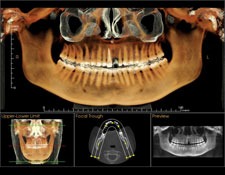

Tomografie computerizată dentară

Tomografia computerizată oferă imagini tridimensionale precise, fiind utilă pentru planificarea intervențiilor chirurgicale dentare complexe sau pentru evaluarea problemelor osoase

Tomografia computerizată dentară (CBCT - Cone Beam Computed Tomography) reprezintă o tehnică avansată de imagistică medicală care a revoluționat modul în care profesioniștii din domeniul stomatologiei pot vizualiza și evalua structurile dentare, maxilarele și mandibulele. În acest articol, ne vom concentra asupra tomografiei computerizate dentare, vom explora tehnologia din spatele acestei metode de imagistică și vom evidenția beneficiile și aplicațiile sale în domeniul stomatologiei.

Tomografia computerizată dentară (CBCT) este o tehnică de imagistică medicală care utilizează un dispozitiv special pentru a obține imagini tridimensionale detaliate ale structurilor dentare și osoase. Această tehnică este bazată pe același principiu ca tomografia computerizată (CT) utilizată în medicină, dar este adaptată pentru a oferi imagini de înaltă rezoluție pentru stomatologie.